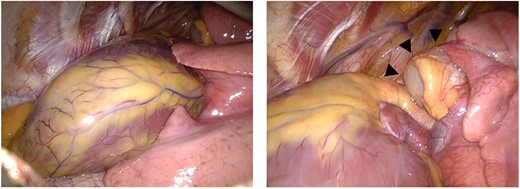

Resection of the cystic mass was performed by video-assisted thoracoscopic surgery with a three-port approach on the left side. As left ventricle and left atrial appendage were directly visualized, the complete absence of the pericardium was immediately observed. The cystic mass arising from the middle mediastinum was attached to the pulmonary artery and visceral pleura of the left upper lobe, and dissected using an electric cautery (Fig. 2). No additional procedure was performed to reconstruct the pericardial defect following the resection of the cyst. The postoperative course was uneventful. The chest tube was removed on the third postoperative day and the patient was discharged on the fifth postoperative day. Pathological diagnosis was a bronchogenic cyst and turbid fluid content was contained in the cyst (Fig. 3).

Intraoperative thoracoscopic images. Complete absence of the left pericardium (left) and cystic mass (arrow heads) arising from the middle mediastinum (right).